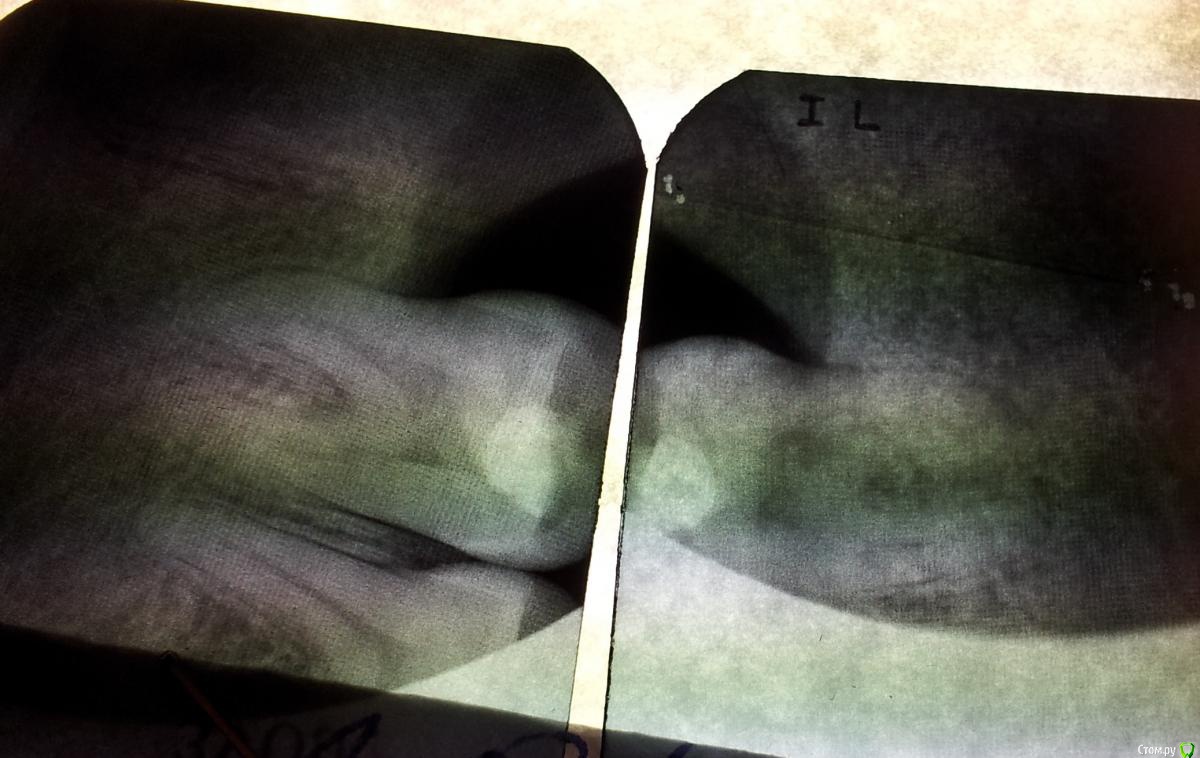

k_d_a Опубликовано 6 ноября, 2015 Автор Поделиться Опубликовано 6 ноября, 2015 Вот снимки. Качество некоторых не очень получилось так что простите. Если будут считать что я очень плохой фотограф то вечером отсканирую ))) Самый первый снимок начал желтеть так что вот.... Ну и из-за того что я снимки фоткал на камеру телефона то одни и те же снимки будут несколько раз чтобы каждый сам выбрал какой лучше. Ссылка на комментарий

red_butler Опубликовано 6 ноября, 2015 Поделиться Опубликовано 6 ноября, 2015 Ваши снимки не помогут. Делайте ОПГ или сразу КТ Ссылка на комментарий